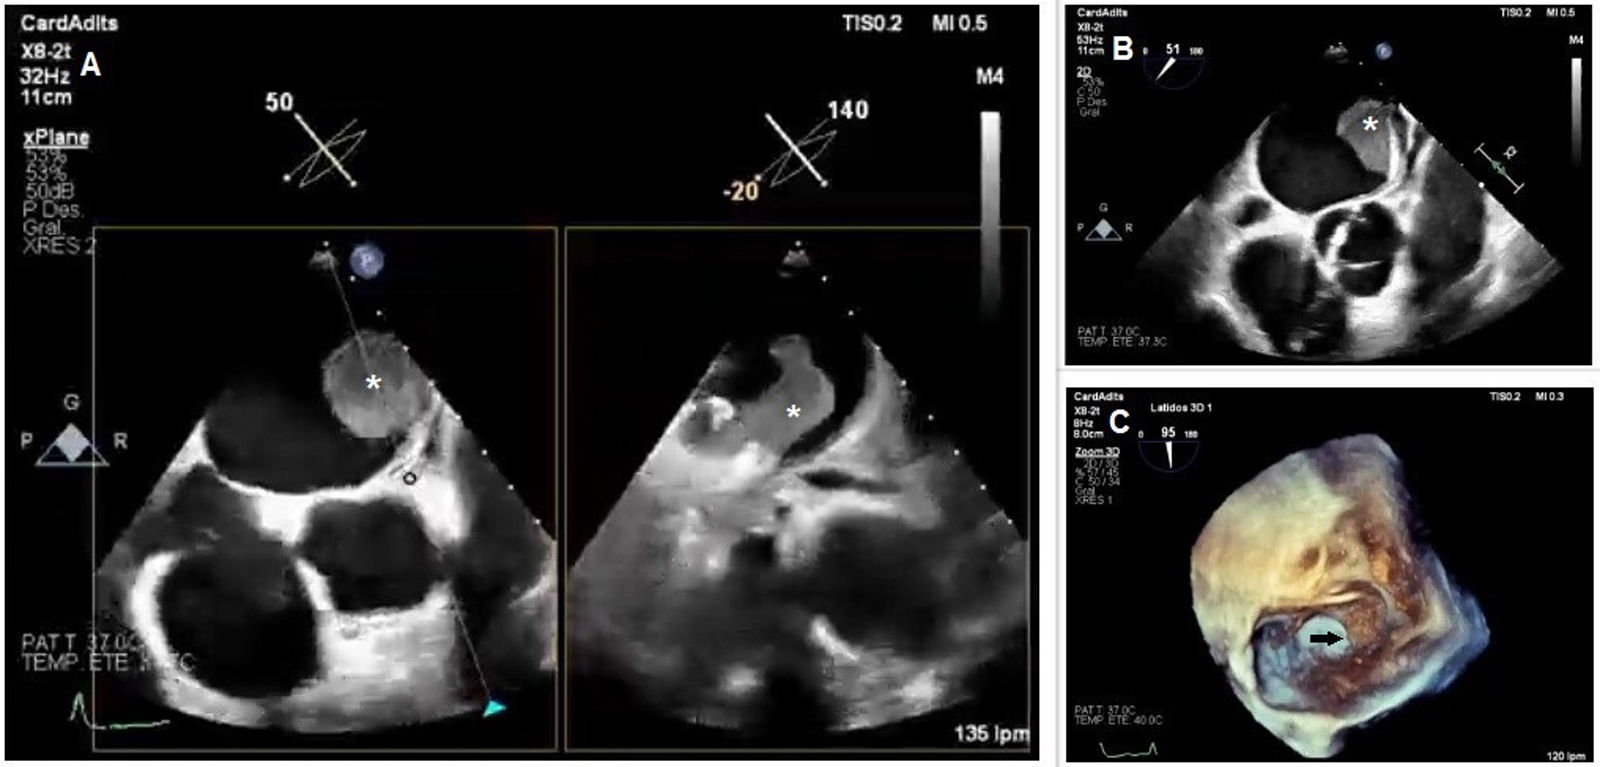

Late thrombosis of a left atrial appendage occlusion in a patient with cancer